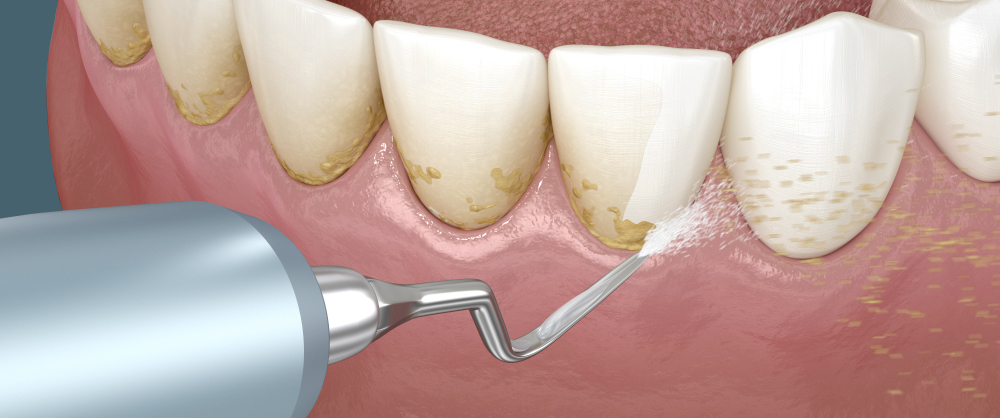

Профессиональная чистка зубов позволяет удалить зубной камень и налёт, которые плохо устраняются при обычной домашней гигиене. Такие процедуры уменьшают риск развития кариеса и заболеваний десен, а также повышают длительность жизни зубов. Кроме того, стоматолог может дать рекомендации, исходя из индивидуальных особенностей пациента, что значительно улучшает качество профилактики.